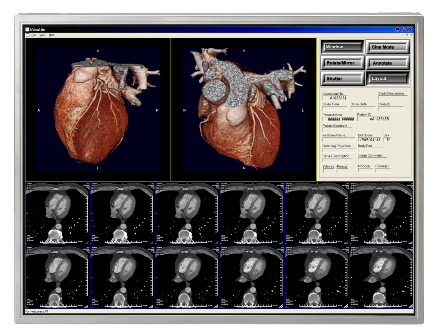

医療現場における液晶表示装置の普及に伴い、液晶表示装置に求められる性能はさらに高度化しています。特にここ数年は医療用画像処理技術が飛躍的に進展し、X線画像などのモノクロ画像と、3D-CT(注1)やFusion(注2)などのカラー画像の両方を読影診断できる高輝度タイプのカラー液晶ディスプレイの需要が高まっています。

注1:CT(Computed Tomography:コンピュータ断層撮影)によって得られた大量の断層画像をコンピュータ処理することによって3Dグラフィック化したもの

注2:CT、PET(Positron Emission Tomography:ポジトロン断層法)、MRI(Magnetic Resonance Imaging:核磁気共鳴画像法)などで得られた画像をコンピュータ処理によって補正しながら重ね合わせ合成したもの。